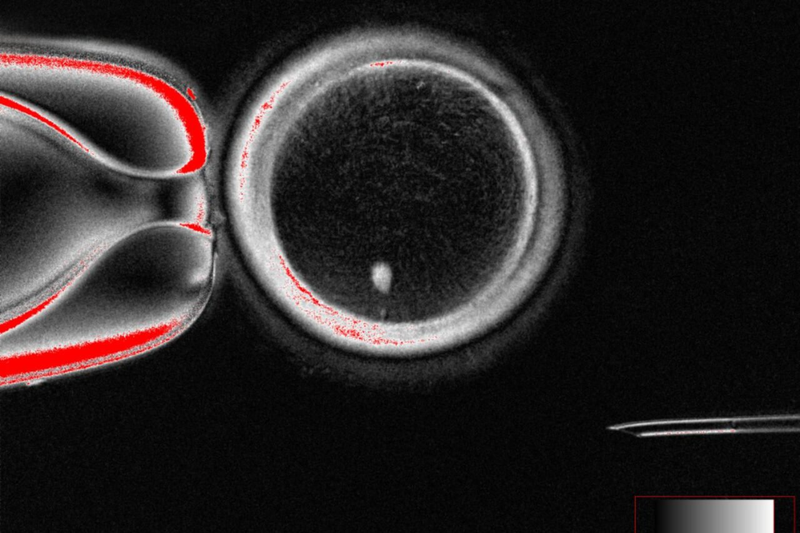

New research shows it's possible to reprogram skin cells into eggs that can be fertilized in the lab, though it's just a proof of concept for now.